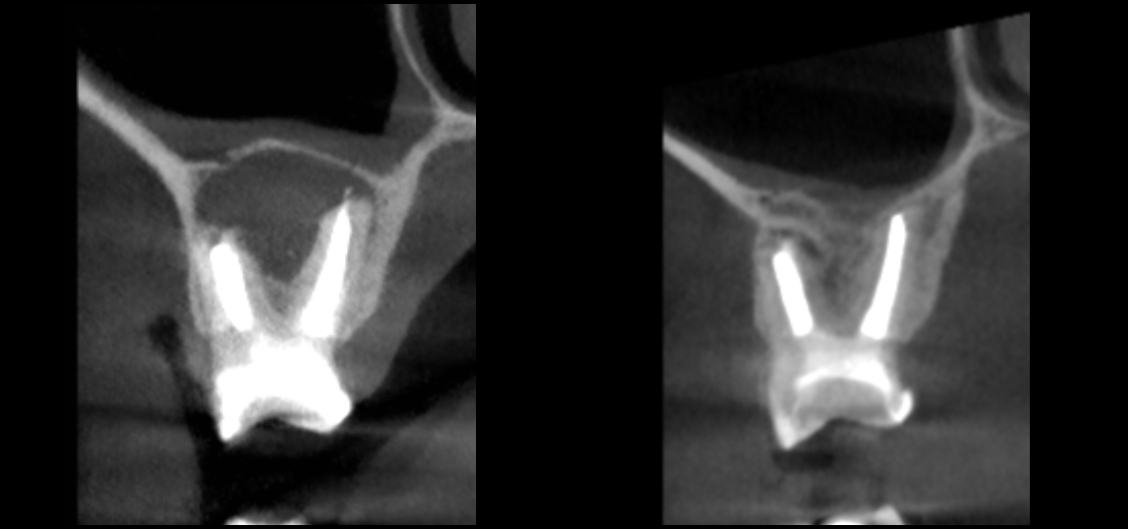

Minęły 4 lata. W marcu 2020 roku pacjent zgłosił się z innym problemem i przy okazji wykonałem tomografię leczonego wcześniej zęba. Rezultat terapeutyczny przedstawiają ryciny 7‑10. Widzimy na nich całkowitą remisję zmiany i powrót fizjologicznej pneumatyzacji zatoki szczękowej w danym miejscu.

Ryc. 7. CBCT – porównanie obrazów zmiany w płaszczyźnie strzałkowej przed i po leczeniu.

Ryc. 8. CBCT – porównanie obrazów zmiany w płaszczyźnie czołowej przed i po leczeniu.